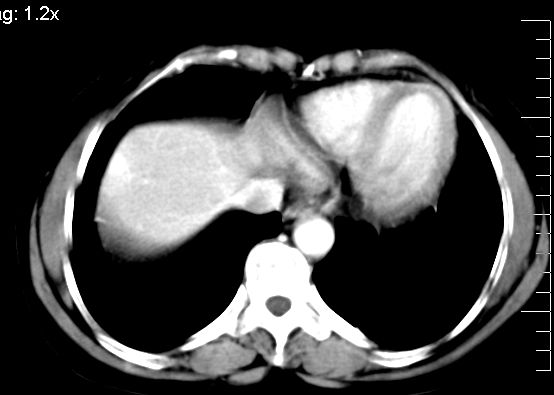

肝大小形态未见异常,肝内外胆管无扩张,肝s8段见一动脉期明显血管样强化结节,门脉期呈高密度,延迟期呈等密度,胆囊不大,增强扫描见胆囊及胆囊颈管壁增厚,有强化。

2、肝s8段结节,考虑小血管瘤。

肝右上叶血管瘤!

考虑肝右叶前上段包膜下小血管瘤。

支持肝右前叶上段小血管瘤